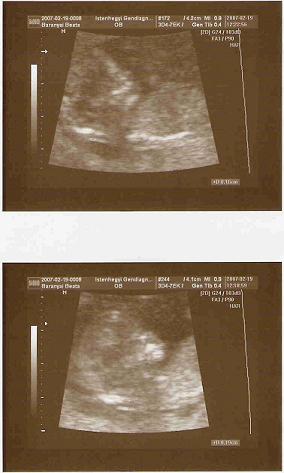

Brigi, nagyon jó hírek a babákról. Szépen látszanak az Uh képeken. :lol:

Brigi,milyen figyelmes a dokid,hogy így odafigyelt a cukorra,de ez a vérnyomás viszont tényleg nagyon magas.Aranyosak a bébik az uh képen.Kis formásak.

Nagyon jók a képek a gyerkőcökről! :D Emlékszem a 12. hét körüli már nekünk is nagy élmény volt! :D